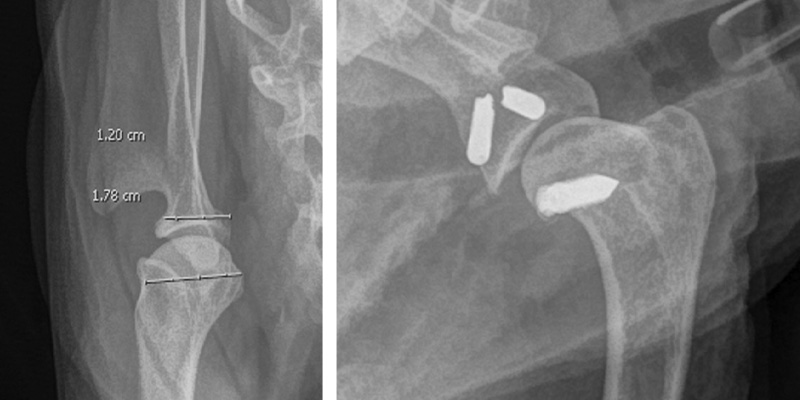

Within this, it was observed there was no significant damage to the cartilage. The surgeon placed implants which anchored the proximal humerus to the medial distal scapula. After strict rest with gentle PROM physiotherapy and hydrotherapy started 3 weeks-post operatively, Martha’s 6-week review highlighted that the lameness was much improved, she was fully weightbearing and walking well 50% more than she had been prior to referral, without the need for analgesia. Martha will return for orthopaedic examination with repeat radiographs if warranted, but in the meantime her owner reports she is doing very well and managing up to 20-minute walks without issue.

Left: pre-op measurements to establish appropriate techniques. Right: Post-op.